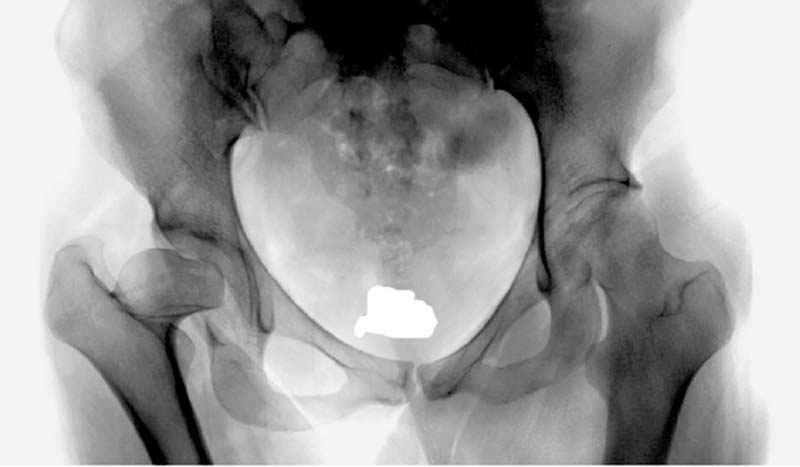

предоперационные снимки #8

|

№ 8-10 предоперационные снимки